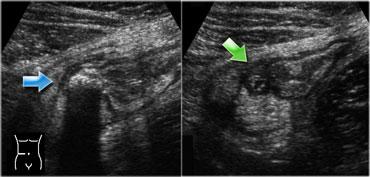

Viêm hồi manh tràng nhiễm khuẩn. Siêu âm cho thấy dày thành lớp niêm mạc và dưới niêm mạc. Đại tràng lên co thắt với hình ảnh bờ múi nổi bật. Ruột thừa bình thường (mũi tên).

Trong viêm hồi manh tràng nhiễm khuẩn, siêu âm cho thấy các đặc điểm khá đặc trưng.

Có hình ảnh dày lan tỏa lớp niêm mạc và dưới niêm mạc của hồi tràng tận và manh tràng.

Ruột thừa phải bình thường trên siêu âm (Hình).

Trái ngược với bệnh Crohn hồi manh tràng, trong viêm hồi manh tràng nhiễm khuẩn, các lớp thành ruột luôn còn nguyên vẹn và lớp cơ cũng như thanh mạc không bao giờ bị tổn thương.